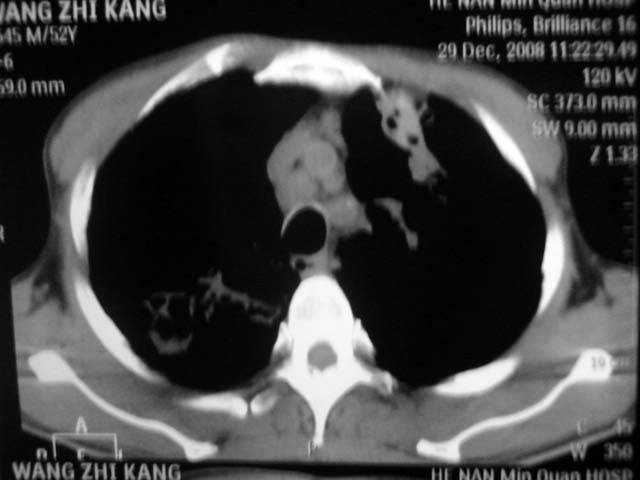

男,52岁,发热2月,糖尿病史。

抗结核治疗irpz方案,血糖未治疗,空腹15.9左右。症状无好转,左胸痛。

复查ct

2、双肺见多发片状及结节状高密度影,大多数病灶中心均见“空泡征”。

3、纵隔内淋巴结肿大。

结果:两肺继发性肺结核并曲霉菌感染。